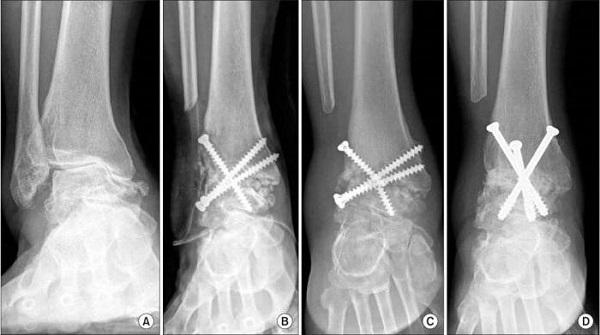

| Фиксация костей | Остеосинтез с использованием пластин, винтов, стержней или внешней фиксации | Неправильное сращение костей, инфекция, повреждение нервов и сосудов, нестабильность фиксации |

Процесс выполнения операции включает следующие этапы:

- анестезия;

- стерилизация инструментов и антисептическая обработка ног;

- разрез мягких тканей;

- удаление нежизнеспособных участков костной и хрящевой ткани;

- формирование сращивания таранной и большеберцовой кости;

- фиксация обездвиженного сустава металлическими штифтами.